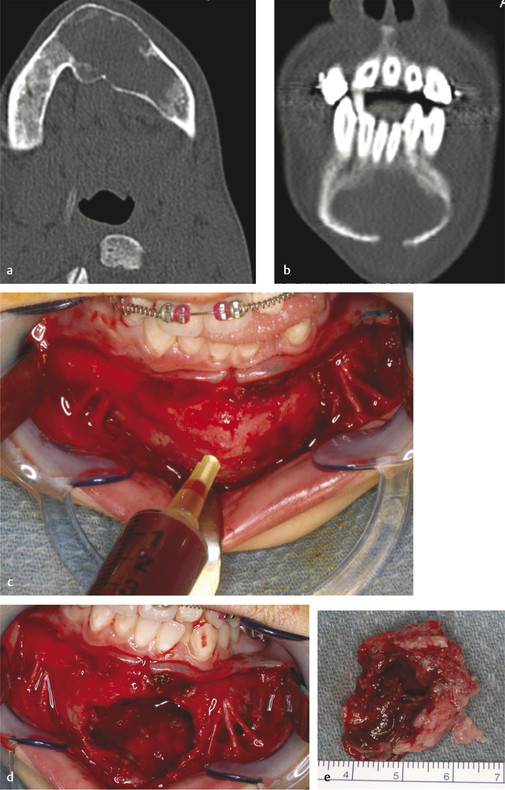

Ameloblastoma is the most common odontogenic tumor, with about 50% of them occurring between 20 and 40 years of age. In the pediatric population, ameloblastoma must be considered in the differential diagnosis of any unilocular or multilocular radiolucency. Unicystic ameloblastoma represents about 5% of all ameloblastomas and tends to occur in younger age range (10–24 years) (Fig. 9‑11a, b). For all ameloblastomas, 80% occur in the mandible and 75% in molar–ramus region. They are benign, locally aggressive, expansile neoplasms that commonly cause dental changes such as mobility, tooth displacement, and root resorption. Untreated tumors can progress to a tremendous size. Treatment involves resection with 1.0 to 1.5 cm bony margins and one uninvolved anatomical barrier (Fig. 9‑11c, d). Consider frozen sections of soft tissue margins as well as taking a radiograph of the specimen to ensure that you have 1-cm margins past radiographic margins (Fig. 9‑11e). Cure rate with resection is about 98%. Controversy exists around immediate reconstruction at the time of resection versus a staged approach. If enucleation and curettage are performed, there is a recurrence rate of more than 80% (Fig. 9‑12).